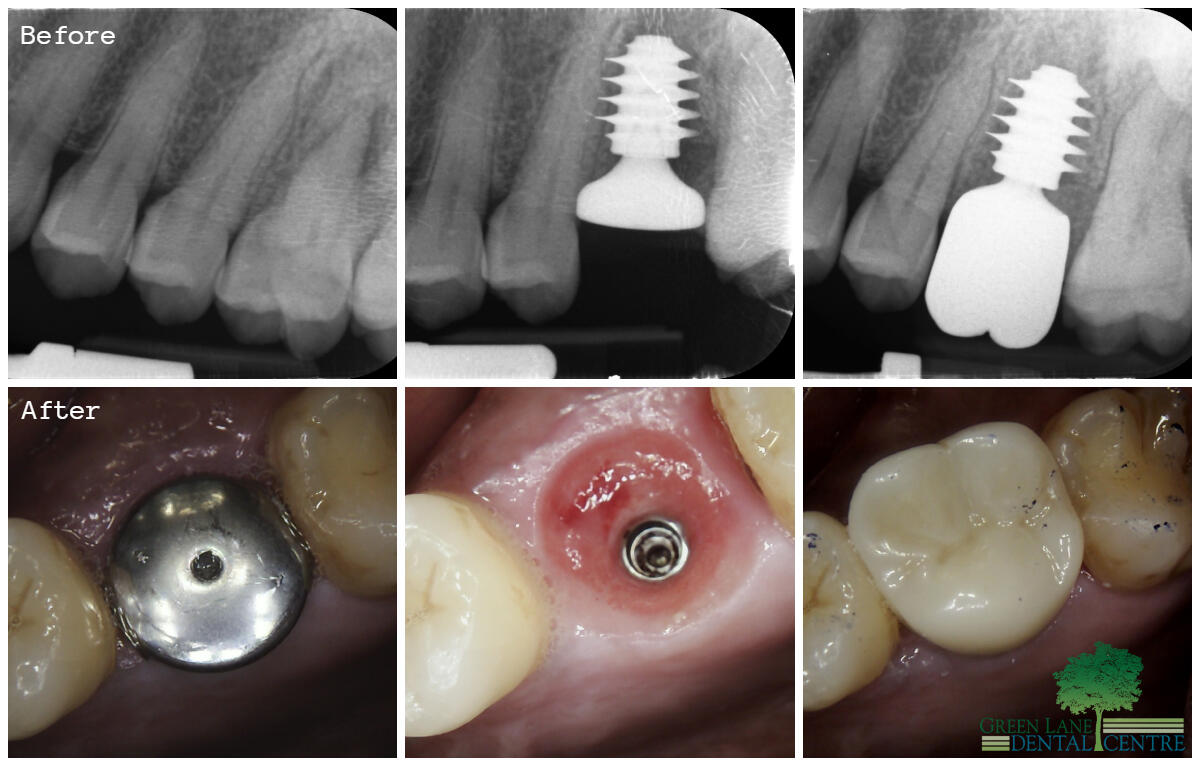

Smile Gallery